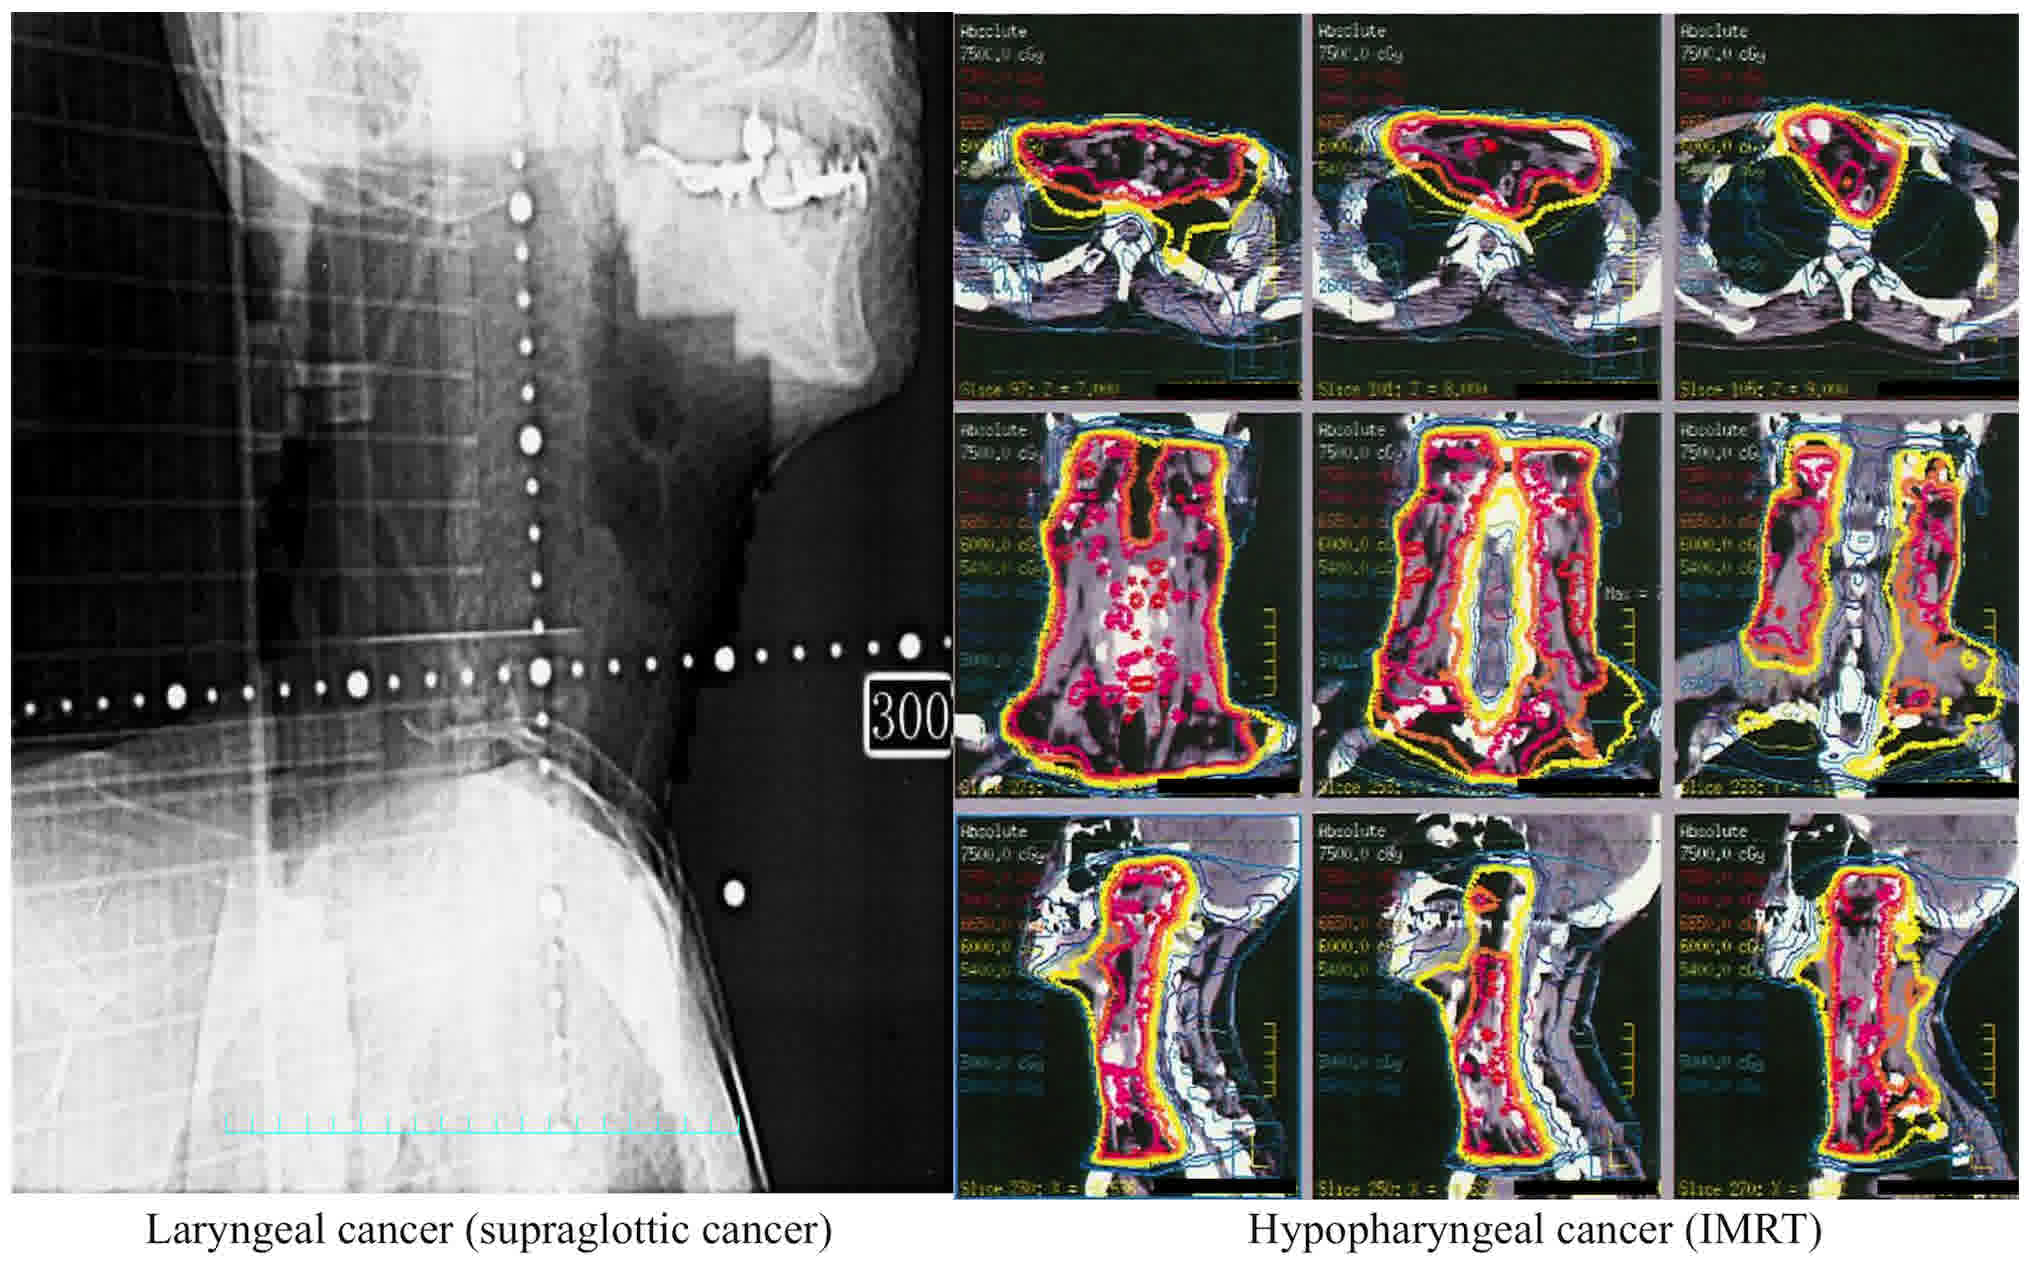

For recurrent cases or residual cases following concomitant chemo‑radiation therapy (CCRT), salvage surgery is a frequently used treatment options. A swallowing disorder is one of the major complications of CCRT. The purpose of the present study was to evaluate the effect of CCRT on swallowing function in patients who underwent salvage total pharyngo-laryngo-esophagectomy (TPLE), and to evaluate the importance of pharyngeal constriction in patients who underwent TPLE. Between 2008 January and 2014 May, 54 patients were treated with salvage TPLE following CCRT or TPLE at the National Cancer Center Hospital East, Chiba, Japan and were included in the present study. A total of 14 patients underwent salvage TPLE following CCRT for recurrence or residual tumor (the salvage TPLE group), and 40 patients underwent TPLE as initial treatment (the TPLE group). The pharyngeal constriction score and the post‑swallowing oropharyngeal residue rate were evaluated, and inadequate velopharyngeal closure was assessed by videofluorography. The pharyngeal constriction score of the salvage TPLE group was poorer than that of the TPLE group (P<0.05). The bolus residue in the oropharynx was significantly larger in the salvage TPLE group than in the TPLE group (P<0.05). With regards to inadequate velopharyngeal closure, there was no significant difference between the TPLE group and the salvage TPLE group (P>0.99). The results of the present study indicate that the swallowing function of patients who undergo salvage TPLE may be affected by CCRT.